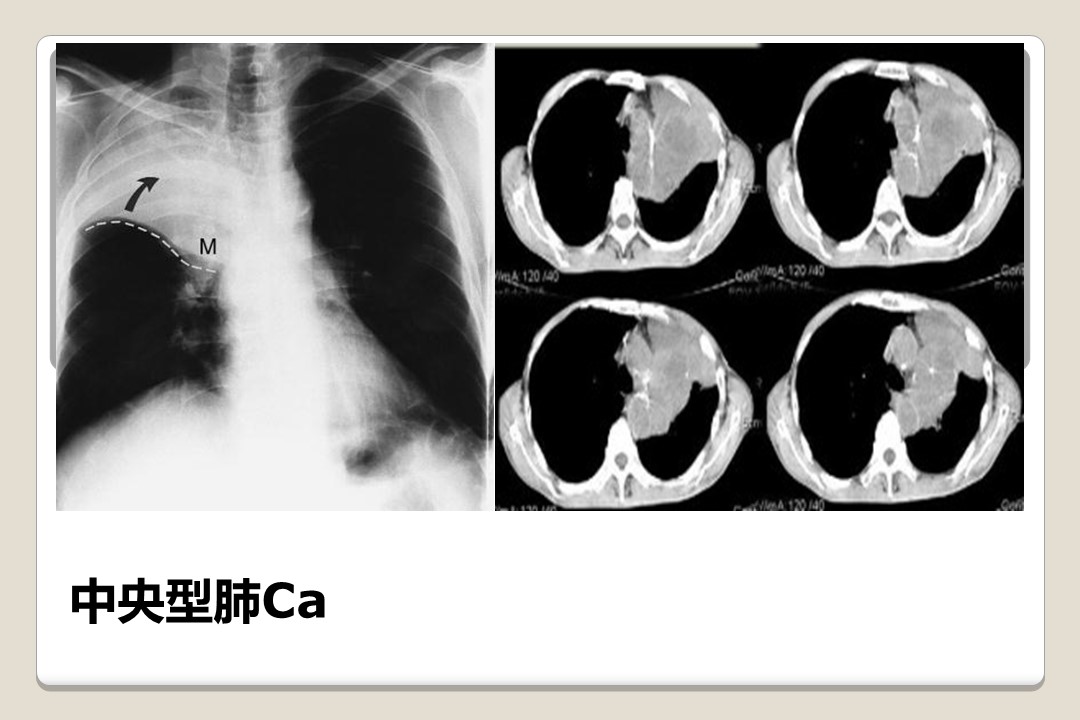

心胸外科常见疾病概述

心胸外科常见疾病概述一、心血管外科疾病 1、先天性心脏病 2、瓣膜病 3、冠心病 4、大血管疾病 5、心包疾病二、普胸疾病 1、胸壁疾病 2、纵隔疾病 3、食管疾病 4、肺疾病 ...